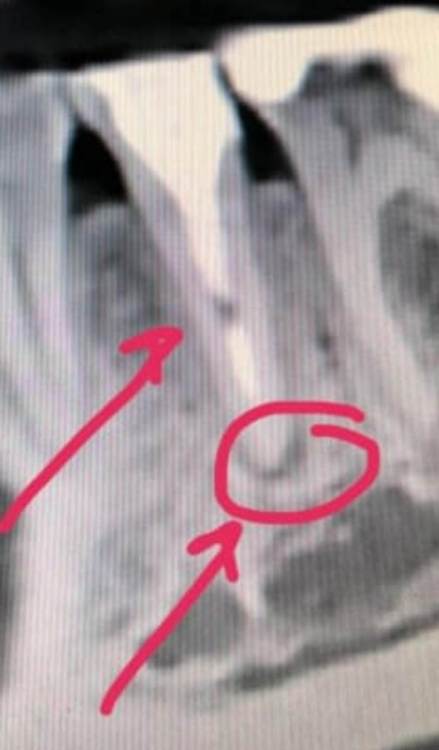

Здравствуйте! По  рекомендации   стомотолога -ортопеда (  решался  вопрос  о  постановке  коронки  на  этот   зуб) мне стоматолог-терапевт провел эндодонтическое лечение периодонтита  в   мертвой "пятерке" на  нижней   челюсти  справа. Провел  фиксацию внутриканальным штифтом и пломбирование корневого канала  зуба методом   горячей гуттаперчи. Сделала   КТ   на  следующий  день, снимки  прикладываю. Появились  вопросы   по  снимкам -что   означает  черное  пятно   в  нижней  трети  канала  после   перепломбировки? И,  как  показывает   снимок,  у  корня   зуба так  воспаление  и  не  ушло. Стоматолог - терапевт принял   решение сразу   перепломбировать  канал, с  установкой   постоянной  пломбы.  Я  думала,  что  мне  поставят   временну  пломбу  ,  и  я  несколько  раз   еще  похожу  на  лечение   к  доктору... Но   доктор  сказал,  что  типа   воспаление    само  пройдет... И  еще,  после   перепломбировки  канала,  стоматолог-ортопед  сказал,  что коронку   теперь  поставить  не  получится,  так  как   тонкие   стенки  и   низкий верх  зуба.

Здравствуйте. Первый рентгеновский снимок после лечения периодонтита делают не ранее 6 месяцев. До этого оценивать качество лечения нельзя, при условии, что вас ничего не беспокоит. Чёрное пятно в канале - просвет заполненный цементом между штифтом и корневой пломбой; либо пора в цементе.